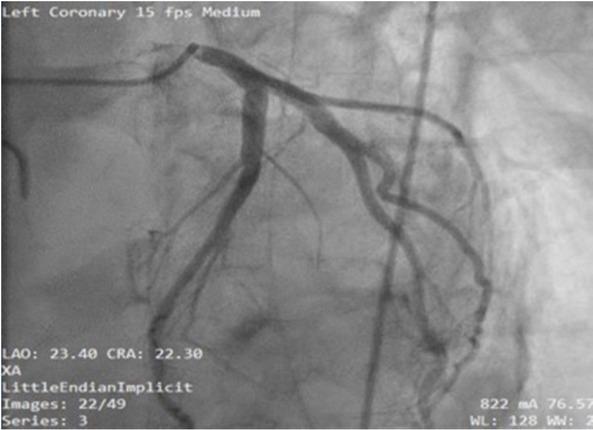

Due to improper TTE windows, a TEE was performed, revealing an acute reduction in the systolic function localized to the base of the left ventricle. The EF was estimated at 35%with mild mitral, aortic, and tricuspid insufficiency. The right ventricle and the apex had normal contractile function (Fig.3). No coronary occlusion was identified during coronary angiography (Fig.4).

Angiography showing no coronary occlusion

Angiography revealed no abnormalities in our patient, in accordance with the modified Mayo criteria [9]. Ghadri et al. developed the InterTak score in 2017, which identified female gender as the most important risk factor for Takotsubo cardiomyopathy. Despite this, our patient was male, demonstrating the importance of knowledge of this disease, regardless of patient’s gender [10].

In our patient, cardiogenic shock, although rare, would have been more likely to occur during surgery, secondary to reperfusion syndrome [18]. reverse Takotsubo cardiomyopathy was diagnosed based on acute onset postoperative cardiogenic shock in the presence of cardiac enzyme abnormalities, ECG changes, and lack of significant coronary angiographic lesions. TEE studies revealed hypokinesis of the ventricular base with no abnormalities on angiography. No clinical signs like dyspnea or retrosternal chest pain were documented.